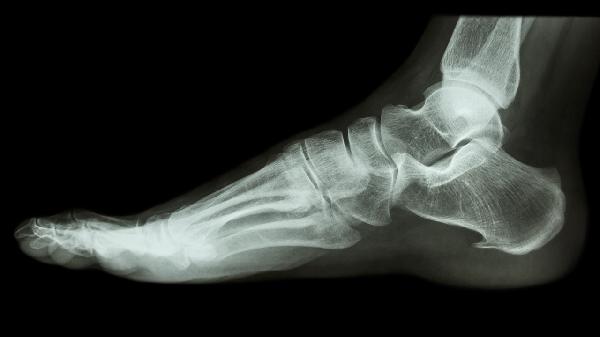

4、溶骨性破坏

X线典型表现为边界清楚的椭圆形透亮区,呈中心性或偏心性生长,周围常有硬化边。病灶内可见散在点状、环状或弧状钙化影,钙化程度与肿瘤分化相关。短管状骨病变常导致骨皮质膨胀变薄,但很少穿透骨膜形成软组织肿块。